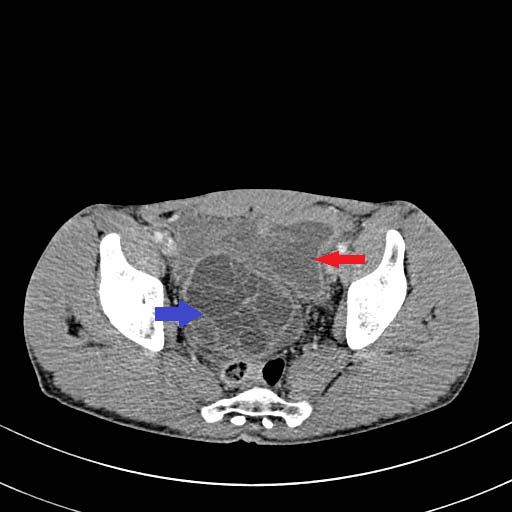

Histology is similar to hamartomas, although some state a lymphangiectasic or neoplastic nature, without any malignant potentiality [3]. Ultrasonography documents mono-or multiloculate fluid-superfluid lesions with a substantial lack of flow with Doppler mode (figure/patient 1-2). Computer Tomography (CT) describes low attenuation masses with occasional fluid level and minimum septal and peripheral enhancement. Magnetic resonance imaging (MRI) detects iso-or hyposignal on T1-weighted sequences and hyper-signal on T2-weighted sequences, a halo of enhancement around the septa of macro-cystic lesions and peri lesional lymphoedema (figure/patient 2-3) [4].

Sclerotherapy is nowadays largely employed in case of macro-cystic or mixed lymphangiomas, where the size of the cysts allows them to be punctured and a wider distribution of the agent is achieved. However, OK-432, bleomycin and above all doxycycline have recently proved effective also with micro-cystic variety [2]. The rationale comes from the observation that lymphangiomas can reduce their size or regress after a spontaneous infection, probably due to the destruction of the epithelium, reduction of lymph production and collapse of the cyst: thus, the idea of adopting sclerosing agents to mimic such an effect. Puncture of the dominant cyst (or more, in case they are noncommunicating) with a fine needle (20 G or more) is followed by aspiration (in order to enhance the SA effect) and injection, in one or more times, of the sclerosing agent, using the same amount as the aspirated fluid (if impossible, half of the lesion's volume). It can be repeated in case of partial response or whenever more administrations are chosen, each session being separated by weeks up to a month. General or loco-regional anaesthesia is preferred in children or uncooperative patients and in adults or small cystic malformations, respectively; the patient's position is changed many times to favour a uniform distribution of the agent and the treatment lasts up to two hours. A postoperative compressive bandage is advised in order to increment the time of contact between the solution and the cyst's wall and to prevent seroma formation, bleeding or effusion of the SA. The procedure can be performed under ultrasound or CT: the first is cheaper, more available, does not employ ionising radiations (thus being advisable in children and young adults), defines better the different components within the lesion, grants different cranio-caudal angles and reduces the risk of accidental puncture of large blood vessels; however, it is operator-dependent and offers a narrow field of view, with the risk of missing some important findings, especially at the post-procedure check. CT instead is easier to perform and provides a more panoramic view but implies radiation and the needle path to lie on the axial plane with its full length [1]; a detailed example of this procedure is offered in figure (patient) 4, whereas figures (patients) 5 and 6 show examples of successful outcomes comparing lymphangiomas before and after sclerotherapy. Fluoroscopic guidance is also reported, especially in case of the most superficial lesions, with the possibility to inject contrast medium into the lesion in order to highlight communications between the intra-lesional spaces and establish the amount of SA to be used [4]. Complications include intraoperative bleeding (due to their dysplastic nature), accidental injuries to nerves, vessels, organs and other tissues (due to extravasation), peri-lesional fibrosis and aesthetic sequelae (due to necrosis followed by second-intention reparation), dosedependent cardio-pulmonary toxicity (especially with bleomycin) and acute respiratory insufficiency (with large lymphangiomas undergoing inflammation, necrosis and quick volumetric expansion); the latter could be managed with dexamethasone or, preferably, avoided by splitting the treatment in more sessions [7]. An example of follow-up program would consist of a clinical examination after one to three weeks, ultrasonography after six to twelve weeks and then (depending on the results of ultrasound) MRI, unless evidence of early recurrence or any other complication occurs [8]. A review by Adams et al didn't prove the superiority of sclerotherapy over surgery but showed it was the treatment of choice in most major paediatric vascular anomaly centres: surgery was reserved for refractory cases, with sclerosing agents not improving either clinics or aesthetics, micro cystic lesions or those associated with life-threatening airway obstruction. Nowadays there are no worldwide-accepted guidelines and patient selection seems to guide the choice. In addition, neither surgery nor sclerotherapy can guarantee complete healing with just one session: it is actually advisable to perform multiple treatments or combine them [1].